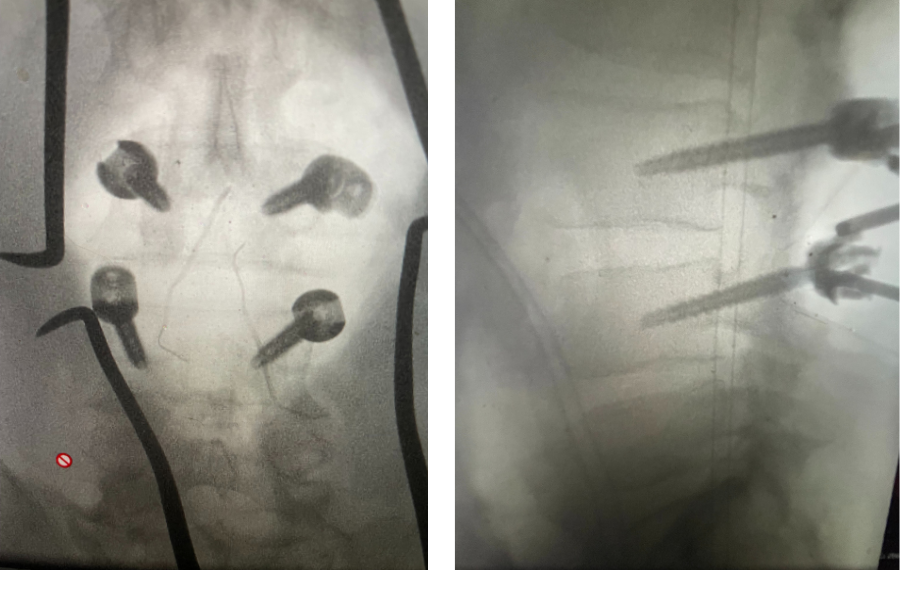

Figure 3. Lateral and AP lumbar intraoperative fluoroscopic images after pedicle screw placement for L3-4 fusion

we augmented our decompression with an instrumented fusion at that level, particularly because of the degree of facet joint removal to adequately decompress him (Fig 3). The facet joints were very overgrown and because of that just undercutting the facet would not prove adequate. These facet joints are enlarged because the patient had degeneration of the cartilage and ligaments of the joints, disc space and supporting structures. A common occurrence is for the spinal segment to slip or “listhes” in Greek. In order to compensate for this instability, the body tries to compensate and enlarges what it has available like the joints and the ligaments. In doing so the spine paradoxically hurts itself in creating spinal stenosis. The bone really does not communicate with the nerve sac and therefore the sac is squeezed because of these enlarged structures. The patient did well postoperatively with relief of his left leg pain and ambulated the same day of his surgery.